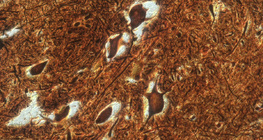

放大200倍